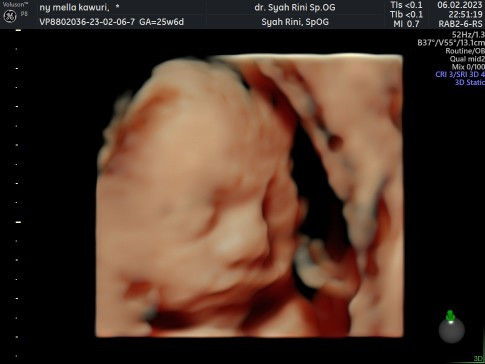

4D abal abal bikin trauma

Saya hamil anak ke 2, usia kandungan 39w. Td malam sy USG beda dokter dr sebelumnya krn kebetulan pindah rumah, nyari yg dekat. Klinik tsb menyediakan USG 4D. Tapi sebenarnya tujuan sy bukan untuk melihat wajah, tp lebih utk memastikan kondisi janin dan peluang sy lahiran normal. USG dimulai, digoyang2 sampai agak keras perut sy. Dokter bersikeras ingin mengubah posisi kepala janin agar mau menghadap depan. Berkali2 digoyang. Krn tdk mau mengubah posisi, sy ditanyain apa sy gak konsumsi DHA?. Sy bilang tidak. Dokter memvonis otak anak sy banyak kosongnya. "Ada otaknya, tapi banyak kosongnya". maka tidak ada respon dan kecerdasannya kurang. Pdhl ada respon tendangan dan gerakan, hanya saja memang bayi tidak mau mengubah posisi/menoleh. Dengan lemas dan syok sy bilang, gpp gak bs foto bayinya. Sy mau mastiin kondisi perut sy. Si dokter tetap berusaha ingin mengambil gambar si bayi tp tetap tdk bs, dan berulang kali menyatakan otak anak sy banyak kosongnya. Pdhl di catatan buku sy, sy sudah pernah 4D dan 3 kali 2D dengan hasil semua normal, lengkap, dan sehat. Gara2 pemeriksaan td malam, sy syok dan sedih berkelanjutan sampai hari ini. Pdhl HPL tinggal seminggu lagi. Perkara tdk mau ubah posisi, respon tendangan tidak digubris. Dan info2 penting mengenai ketuban, lilitan, ari2, kalau tdk ditanyakan jg tidak dipentingkan. Selalu menekankan otak bayi sy banyak kosongnya, entah benar atau tidak benar 😭 Astaghfirullah.... Foto 1, USG 4D usia 28w. Dokter menyatakan semua organ lengkap, normal. Foto 2, USG 4D 39w. Lebih ky foto minyak goreng. Harganya jg jauh lbh murah.